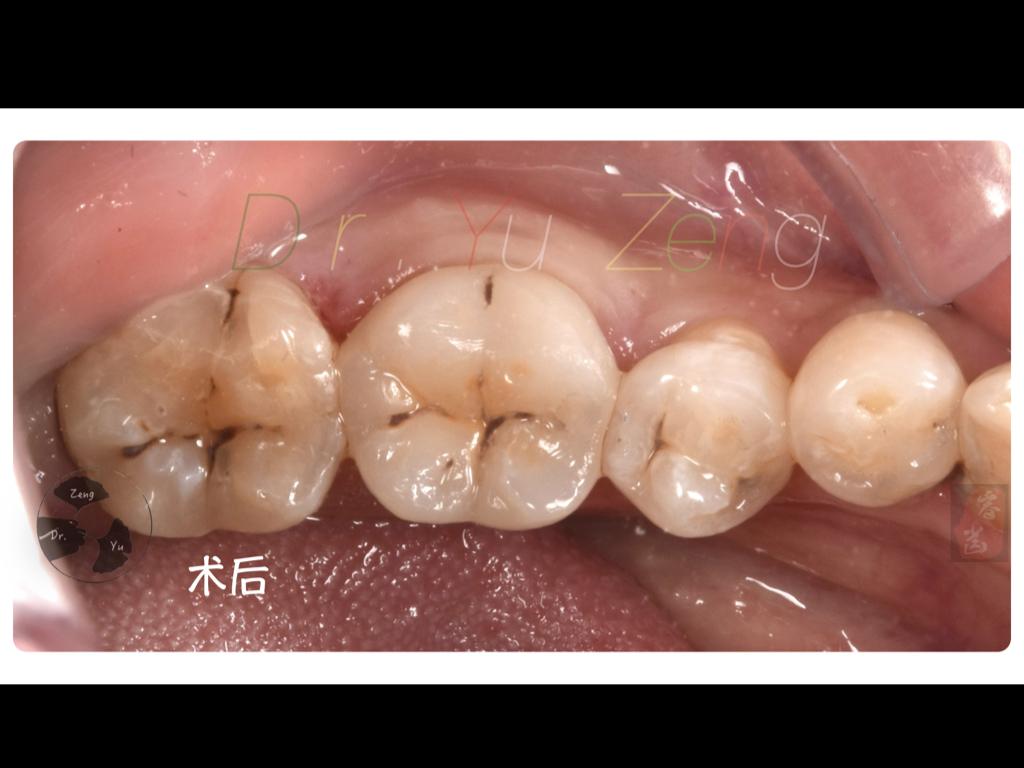

铸瓷嵌体

牙医 曾煜 技师 朱思琪